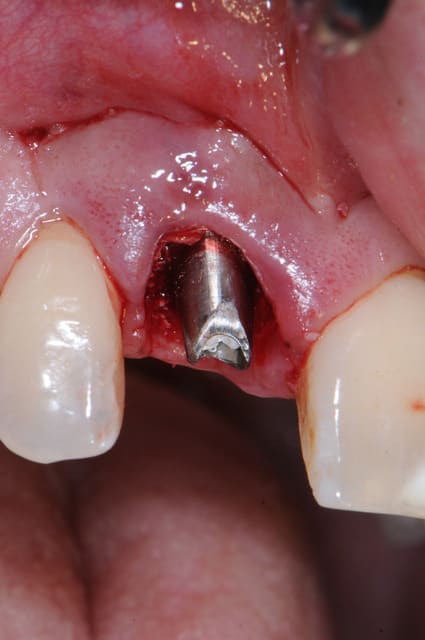

Dsc 0964 qivimn - Eugenol

La photo #4 montre l'implant en position finale ?

Oui, l'implant est en position finale sur la photo 4.